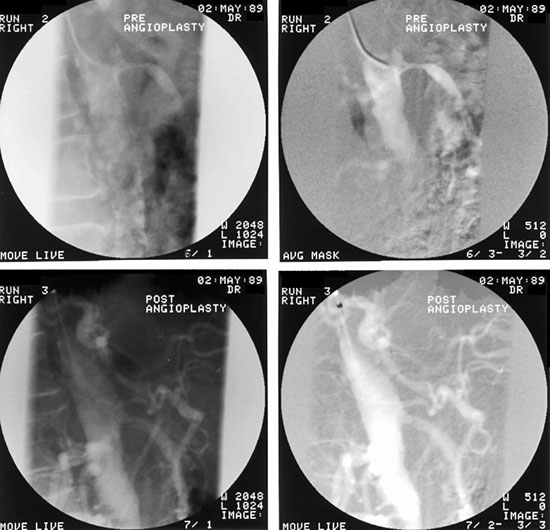

The most favourite subspecialty was angiography and interventional work particularly in the vascular field. This was the first angioplasty performed in the department. This represents atheroma with a focal stricture of the left femoral artery which was dilated with the presented result. Note that the atheromatous process is not limited to one area.

Femoral artery stricture post dilatation. Note the ragged appearance of the dilated atheromatous plaque.